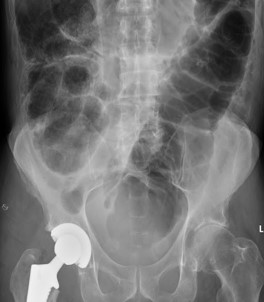

Figure 2: Sigmoid volvulus (Plain x-ray).

Coffee been sign

When the redundant sigmoid colon becomes symptomatic, the differential diagnosis is ‘acute colonic pseudo-obstruction’ which is associated with ‘intestinal neural dysplasia’ [9]. The erect plain abdominal x-ray appears different from that of a sigmoid volvulus (Figures 2 & 3).